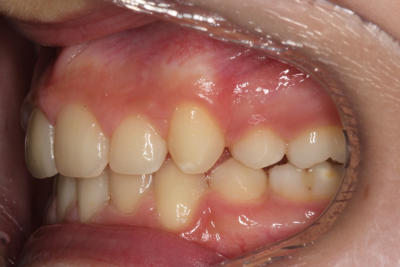

Crowding – Child case